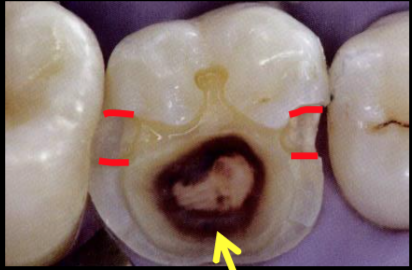

reduction of weakened cusps

fracture strength increases when cusps are covered (removed or reduced)

Rules for Cusp removal

if unsupported tooth structure OR caries extension from primary groove to cusp tip (up the cusp incline) is:

1/2 the distance: NO removal is indicated

1/2 to 2/3 the distance: consider cusp removal

over 2/3 the distance: remove the cusp

Cusp Reduction

Remember amalgam needs 2.0 mm for sufficient bulk - for resistance to fracture

reduce cusps to give enough space - 2.0 mm